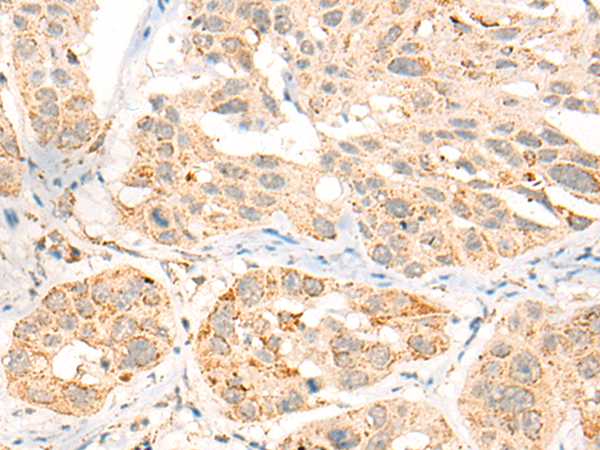

分类: 科研抗体货号: P09491别名: CFP1; CGBP; SPP1; PCCX1; PHF18; hCGBP; ZCGPC1; HsT2645; 2410002I16Rik; 5830420C16Rik应用: IHC反应种属: Human, Mouse